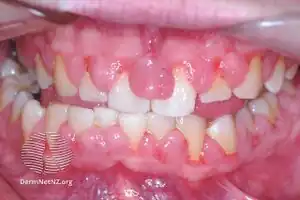

| Gingivitis, a common cause of inflammatory gingival enlargement. | |

Inflammatory enlargement

Gingival enlargement has a multitude of causes. The most common is chronic inflammatory gingival enlargement, when the gingivae are soft and discolored. This is caused by tissue edema and infective cellular infiltration caused by prolonged exposure to bacterial plaque, and is treated with conventional periodontal treatment, such as scaling and root planing.[1]

Gingivitis and gingival enlargement are often seen in mouth breathers,[4] as a result of irritation brought on by surface dehydration, but the manner in which it is caused has not been demonstrated.[1]

The accumulation and retention of plaque is the chief cause of inflammatory gingival enlargement. Risk factors include poor oral hygiene,[5] as well as physical irritation of the gingiva by improper restorative and orthodontic appliances.[1]